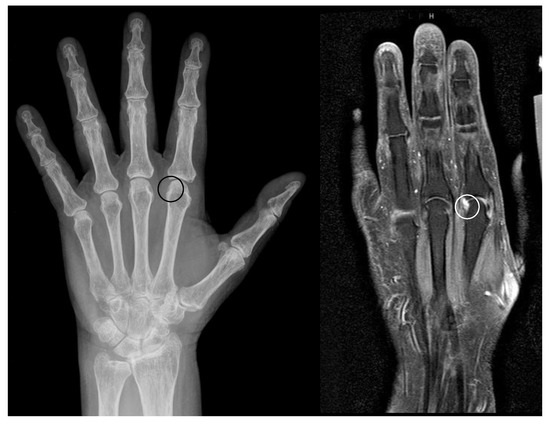

Figure 5. Erosions within pseudoerosions. Example of the development of an erosion within a pseudoerosion (black/white circle) in a left hand of a 65 years old female patient with longstanding mild seropositive rheumatoid arthritis. Left: radiograph, right: MRI.

4.3. Erosions-in-Pseudoerosions

Both anatomic and artefact-related pseudoerosions are located at sites with direct or indirect contact to inflammatory tissue in arthritis, and therefore, are at higher risk for destruction. Areas of the articular bone without any cartilage covering are more prone to erosive destructions by synovial tissue and effusion [3,32]. Hence, in an anatomically preformed concavity a true inflammatory erosion may develop. McQueen et al. [51] described these erosions-in-pseudoerosions (Figure 5) for the attachment sites of the intercarpal ligaments. It may be observed at the site of ligamentous attachments covered by synovial folds at the metacarpal or metatarsal heads or at the wrist. On the other hand, true erosions may be classified as normal variants. It remains unclear whether these are incidental findings or subclinical erosions [3,57,102].